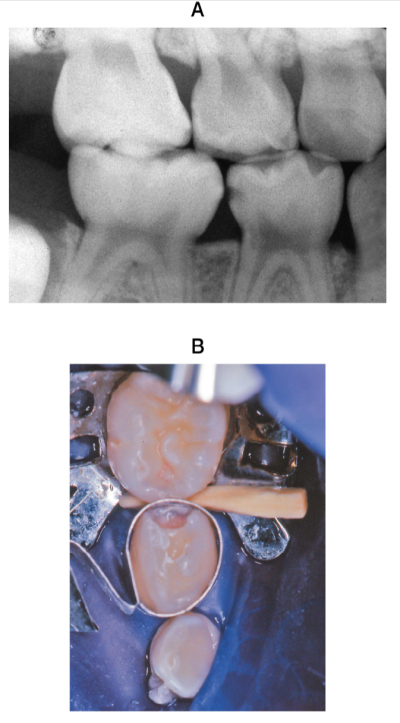

5歳の男児。下顎右側第一乳臼歯の疼痛を主訴として来院した。3日前から一過性の冷水痛があるという。象牙質齲蝕と診断し、ワンステップ接着システムを用いたコンポジットレジン修復処置を行うこととした。初診時のエックス線画像と術中の口腔内写真を別に示す。

この後行う治療内容を実施の順番に並べよ。

解答: 【①】 → 光照射或 → 【②】 → 光照射或 → 【③】 → 【④】 → 【⑤】

a. 咬合調整

b. 歯面処理

c. 隔壁の除去

d. ウェッジの除去

e. 光重合型コンポジットレジンの塡塞